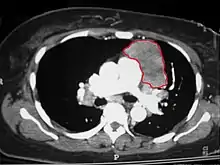

| An encapsulated thymoma (mixed lymphocytic and epithelial type) | |